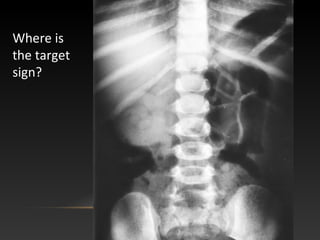

Where is

the target

sign?

Created by gas

trapped between

two layers of

intestinal wall

target sign